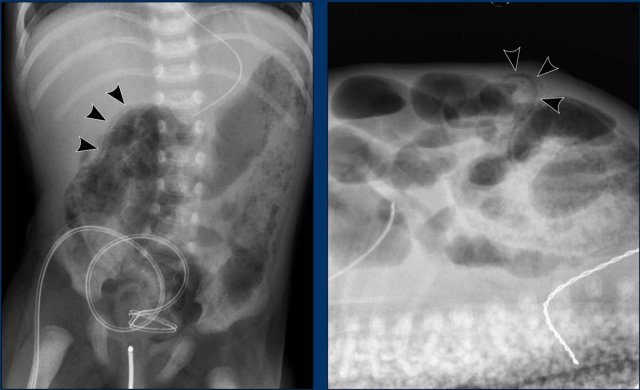

Images

Two radiographs taken several hours apart with in the upper abdomen only slightly dilated, but featureless loops, not changing over time. This is a sign of absent peristalsis.

Recommended repeat schedules are between 6-8 hours, but are of course dependent on the clinical situation.

Another example of persistent loops.

Scroll through the images.